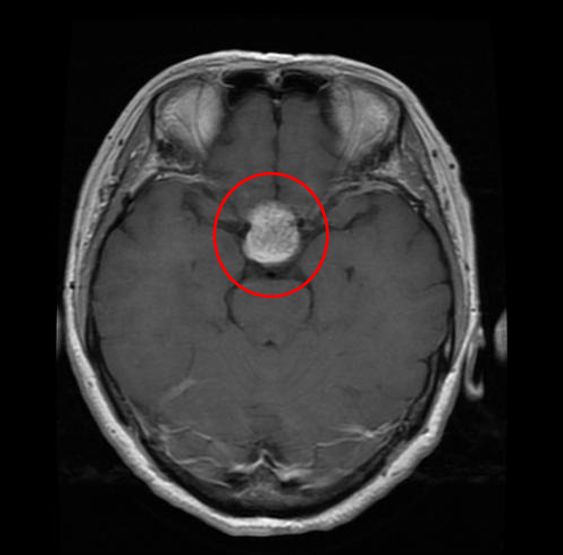

## 2. Meningioma Tumor: A meningioma is a tumor that arises from the meninges — the membranes that surround your brain and spinal cord. Although not technically a brain tumor, it is included in this category because it may compress or squeeze the adjacent brain, nerves and vessels.Pituitary tumors are abnormal growths that develop in your pituitary gland. Some pituitary tumors result in too much of the hormones that regulate important functions of your body. Some pituitary tumors can cause your pituitary gland to produce lower levels of hormones.